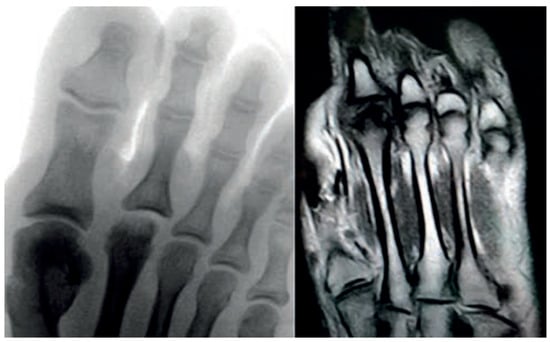

Plain radiographs are the cornerstone of imaging in the diagnosis of lesser metatarsal osteochondrosis. In the early stages of the disease, when supported by a suggestive clinical presentation, obtaining a comparative radiograph of the contralateral foot can be a useful diagnostic tool (Figure 9).

Figure 9.

Radiograph of a symptomatic 10-year-old female patient showing early sclerosis and flattening of the second metatarsal head on the left foot, compared to the contralateral side.

In the later stages, radiographs may reveal characteristic changes including subchondral sclerosis, fragmentation, and flattening of the affected metatarsal head (Figure 10 and Figure 11). In some cases, the presence of joint space narrowing or bony irregularities may also be observed. However, early changes, such as bone marrow edema or subtle cartilage damage, may not be visible on standard radiographs. MRI is particularly useful in the early stages of the disease, as it can detect bone marrow edema, which is a sign of active bone inflammation and necrosis, even before structural changes become apparent on radiographs (Figure 10, Figure 11 and Figure 12).

Figure 10.

Radiograph (left) and MRI (right) of a 17-year-old female patient showing necrotic changes and initial flattening of the second metatarsal head.

Figure 11.

Radiograph (left) and MRI (right) of a 15-year-old male patient with osteochondrosis of the third metatarsal head and early signs of deformation.

Figure 12.

MRI of a 12-year-old female patient showing extensive bone marrow edema of the third metatarsal head, consistent with active inflammation and necrosis.